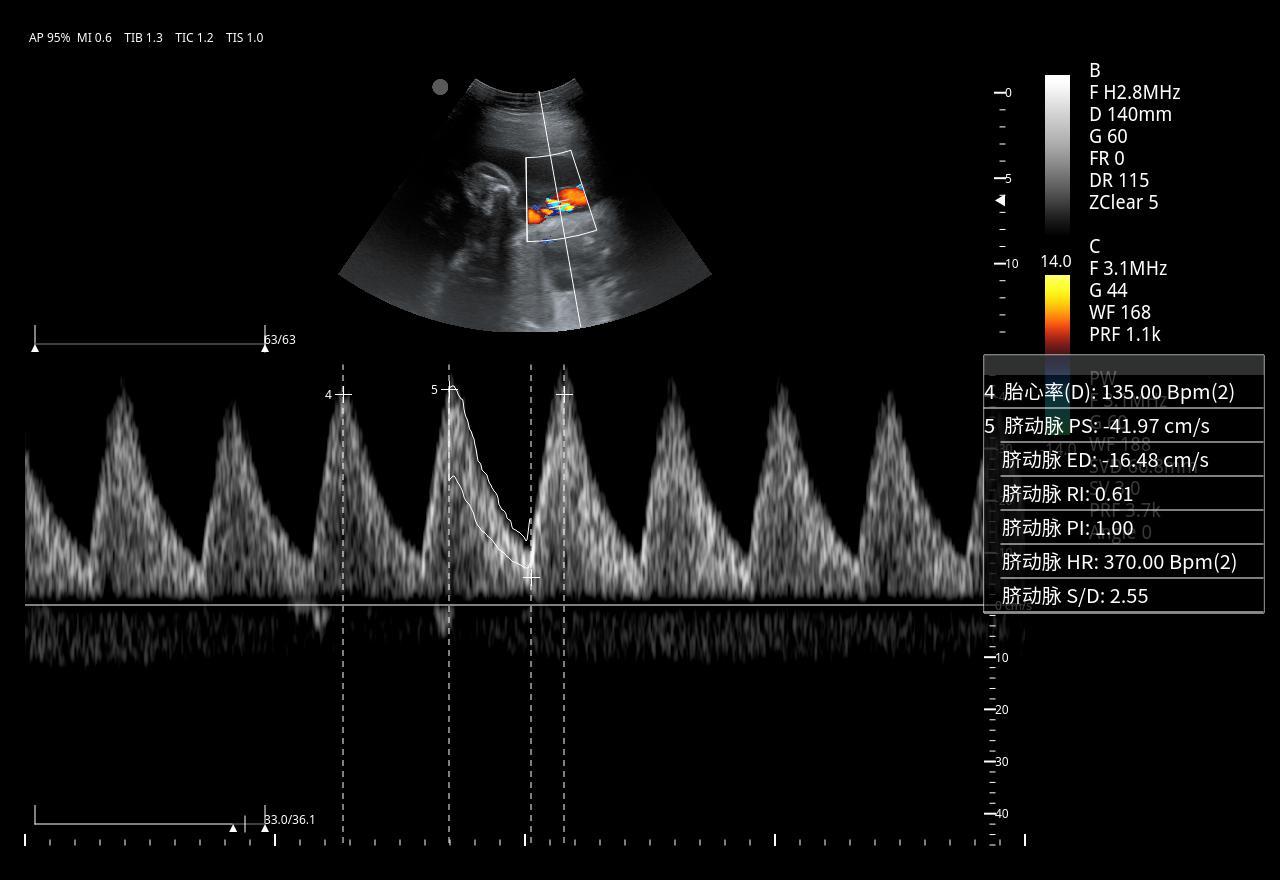

Imágenes clínicas extraordinarias

El Doppler Color ViV 20 es un ecógrafo de nueva generación diseñado para ofrecer una experiencia clínica superior con un equilibrio perfecto entre rendimiento, durabilidad y accesibilidad. Su arquitectura avanzada proporciona imágenes claras y precisas, permitiendo diagnósticos confiables en aplicaciones como abdomen, ginecología, vascular, partes blandas y más.

Práctico y fácil de usar, el ViV 20 integra funciones esenciales para el trabajo diario, con herramientas de medición completas, modos Doppler avanzados y optimización automática de imagen. Su diseño resistente garantiza una larga vida útil incluso en entornos de alta demanda, convirtiéndolo en una opción ideal tanto para clínicas pequeñas como para centros médicos con gran flujo de pacientes.

| Aplicaciones | Cardiología, abdomen, vasos sanguíneos, estudios generales |